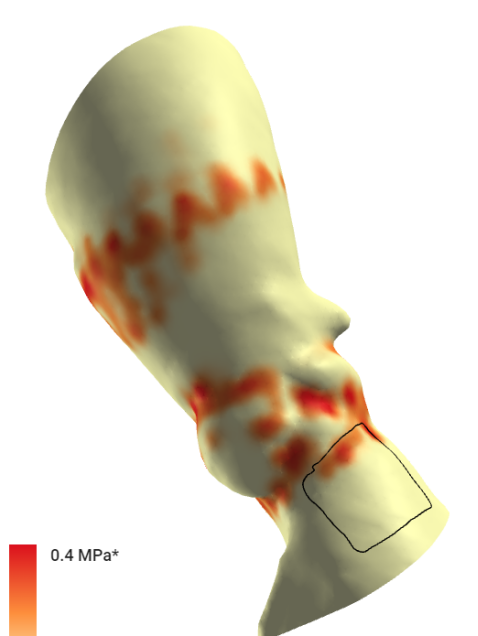

根据FEops评估报告得知,L26号瓣膜在高位和标准位释放之后,分别会发生21%和29%的接触压力指数,均大于FEops评估有无传导阻滞的临界值14%,其中L26号瓣膜高位释放结果虽然比标准位释放结果略好,但是发生传导阻滞的可能依然很大,建议术中使用A+减少风险,必要时术后留置起搏器观察。

L26号瓣膜高位植入后主动脉受压情况

L26号瓣膜标准位植入后主动脉受压情况